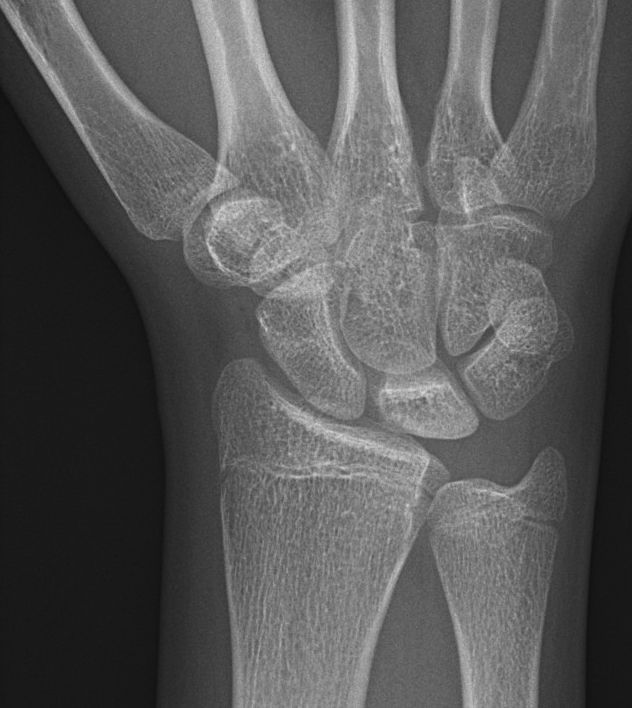

Stadium 3A: Kollapsad lunatum, kapitatum förflyttad proximalt [2]

Slätröntgen och T1-viktad MR-bild av lunatummalaci stadium 3A